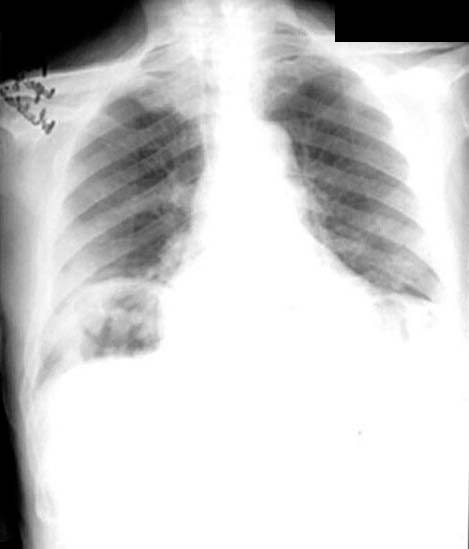

Cavity

• Large

• Thick walled

• Irregular lumen

• Stalagmites